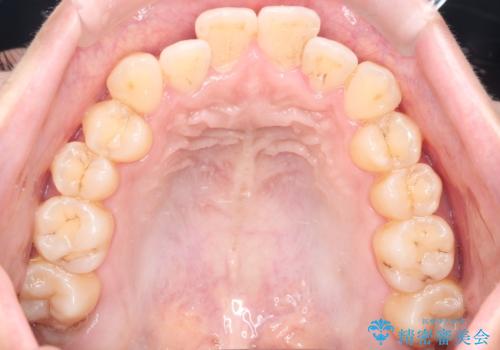

- 前歯のガタガタ(叢生)と、前歯が出ている(突出している)ことを気にされてご来院されました。精密な検査の結果、歯が並ぶスペースと、前歯を引っ込めるスペースの両方が不足していると診断。患者様のご希望に合わせ、透明で目立ちにくいインビザライン(マウスピース矯正)による治療計画を立案しました。スペースの確保は、奥歯全体を奥へ動かす遠心移動と、歯の側面をわずかに削る**IPR(歯間乳頭保護下ストリッピング)**を組み合わせて行い、前歯を効果的に引っ込めることを目指します。

今回の矯正治療では、透明なマウスピース型の装置インビザラインを使用しました。前歯を無理なく引っ込めるスペースを作るため、まず奥歯全体を後方へ移動させる遠心移動を実施。さらに、安全性が確保できる範囲で歯の側面をわずかに削るIPRを併用し、必要なスペースを確保しました。これらの処置により、前歯のデコボコが解消され、前に出ていた前歯も適切に引っ込みました。目立たない装置で治療を完結することで、叢生と突出感が解消され、機能性と審美性が向上した美しい口元を獲得していただけました。